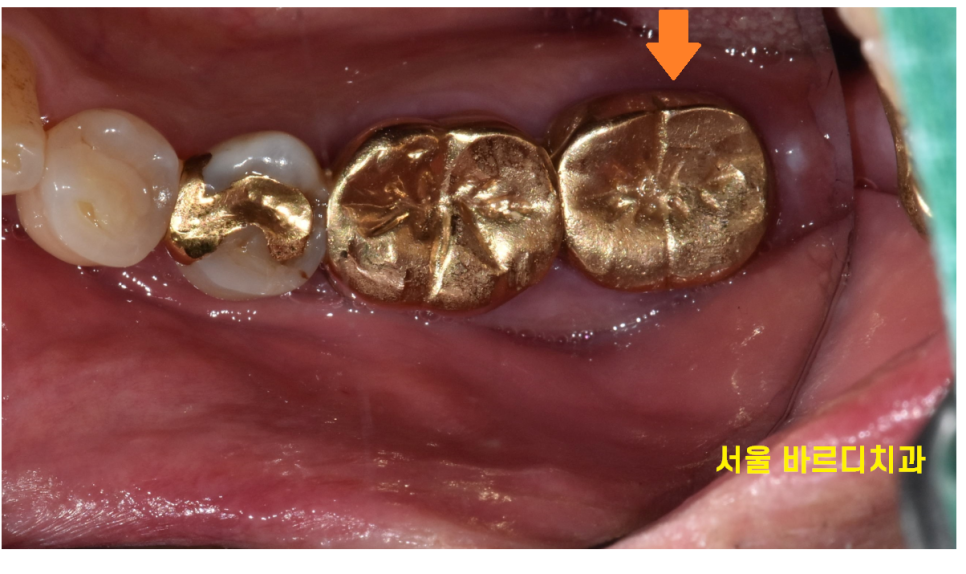

환자분은 보철을 씌운 치아에 충치가 발생했습니다.

잇몸과 보철 경계부위가 양치가 잘 안되고 하다보니

세균과 음식물이 붙으면서 충치가 생긴듯 합니다.